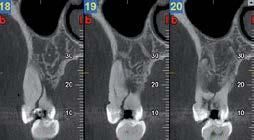

Nell’ambito della radiologia 3D ortopedica, il centro diagnostico utilizza il nuovissimo macchinario NewTom 5G XL, in grado di individuare con la massima precisione la presenza di fratture o lussazioni delle articolazioni, controllare la corretta guarigione di una frattura, valutare una lesione o una ferita causata da infezione, artrite o crescita anormale dell’osso.

Il tutto mediante una semplice e veloce scansione, grazie alla quale si otterranno diverse immagini in 3D ad altissima risoluzione e, per ottenere immagini ancora più nitide mediante un bassissimo dosaggio di radiazioni, gli esperti si avvalgono dell’innovazione racchiusa nella tecnologia Cone Beam.

Se con la radiologia tradizionale era necessario eseguire scansioni multiple, la novità introdotta dal macchinario NewTom 5G XL risiede nella capacità di fornire immagini ad alta risoluzione in un’unica scansione, mostrando nitidamente i dettagli delle articolazioni degli arti superiori e inferiori. Inoltre, a differenza della tecnologia 2D, la radiologia 3D ortopedica permette di individuare immediatamente alcune patologie come quella del metatarso, la quale richiede un allineamento visivo dedicato o una diagnosi delle micro fratture ossee.